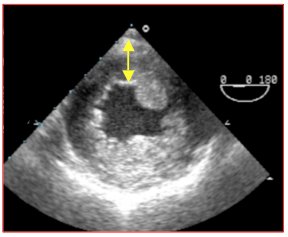

L’augmentation de postcharge induit une hypertrophie concentrique du VG (HVG), dont la paroi s’épaissit (> 1.2 cm en diastole) et la cavité se rétrécit (Vidéo et Figure 26.107). L’absence d’HVG concentrique est le marqueur d’une inadaptation du ventricule, d’une dysfonction gauche ou d’une sténose peu importante.

Vidéo: vue court-axe transgastrique d'une hypertrophie concentrique sévère du VG sur sténose aortique serrée.

Figure 26.107 : Hypertrophie concentrique du VG dans un cas de sténose aortique serrée. L'épaisseur de la paroi postérieure est de 1.5 cm en diastole. La cavité du VG est très rétrécie.